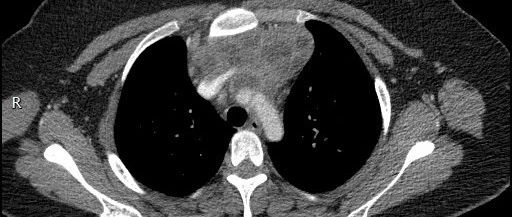

医学影像 yxyx-app 医学影像APP,打造伴随医生快速成长的影像学习社区。与影像园(Xctmr.com)一起提供最全面的影像案例库、基础(解剖、病理、影像诊断)知识、影像技术及考题等,为医生提供最佳的医学影像参考。【所属科室】呼吸科【基本资料】患者,女,20岁【主诉】干咳伴胸痛半月【影像图片】【讨论问题】如何诊断?【医学影像APP用户讨论】评论:左前纵隔见一囊样包块影,内见结节状、条片状脂性密度影,局部囊壁见壁结节影,增强见囊壁及壁结节明显均匀强化;上纵隔脂肪间隙密度增高,但与包块分界尚清,增强后内未见明显强化;肺动脉主干及左侧肺动脉见受压推移,未见充盈缺损影。前纵隔占位,考虑畸胎瘤。...